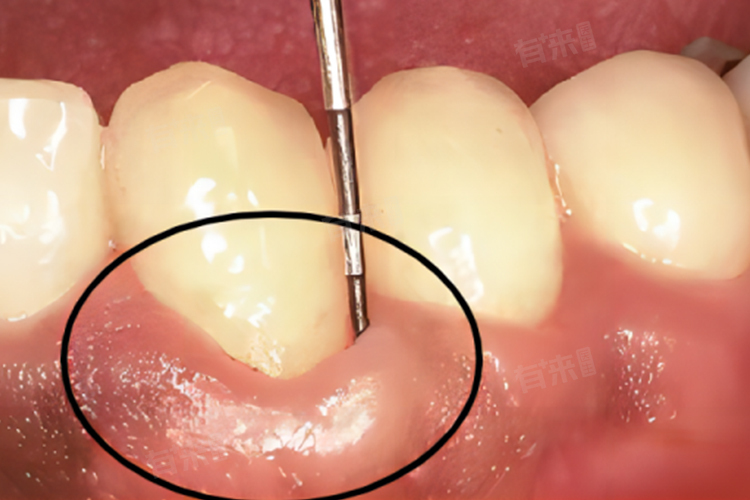

2、中度牙周袋:当中度牙周炎发生时,牙周袋的深度会加深至4至6毫米,牙龈炎症更加明显,可能出现牙周脓肿,牙齿也可能出现轻度松动。中度牙周炎的病情更为严重,治疗难度也相应增加。建议进行口腔卫生教育和洁牙,可能还需要在专业医生的指导下进行牙周手术治疗,如牙周翻瓣手术,以清除病变组织,恢复牙槽骨的高度。